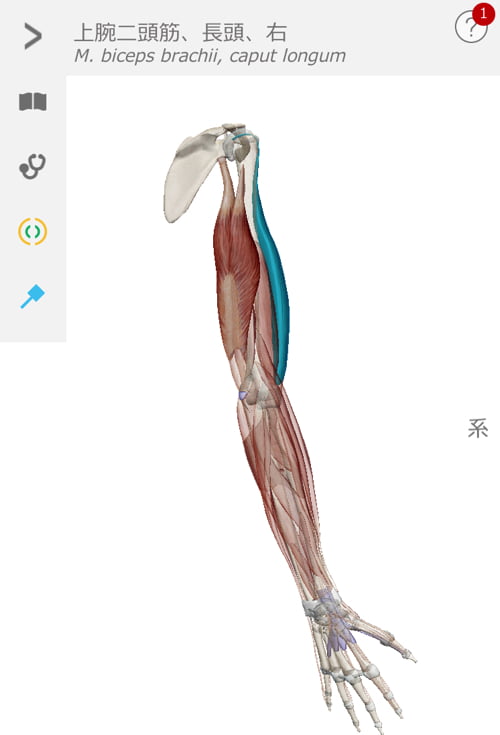

肘がネジレるとこんな感じで繋がっている肩や肩甲骨の位置にずれが生じます。

超精密に出来ている私達の身体はネジレやズレができると

危険回避の為に痛みが出て動かせなくなります。

脇の周りの筋肉も硬直していて腕が上がらない、回せない

動かすと痛い症状を作っていました。